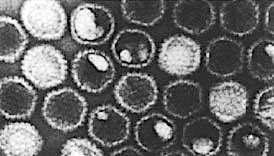

アヒルA型肝炎ウイルス(DHAV)1(以前はDHV-1と呼ばれていました)は、アヒルウイルス性肝炎(DVH)を引き起こす3つのウイルスのうちの1つで、若いアヒルの急性で高伝染性、しばしば致死的なウイルス感染です。

DHAVは、3つのウイルスの中で最も毒性が強く、生後3週間未満のアヒルでは最大95%の死亡率に達します。

ピコルナウイルス属(アビヘパトウイルス)に分類されるDHAV-1は、生後3週間未満のアヒルで最大95%の死亡率に達する可能性がある最も毒性の高いウイルス型です(マラードとペキン種のみ)。

科:ピコルナウイルス科(Picornaviridae)

属:アビヘパトウイルス(Avihepatovirus)